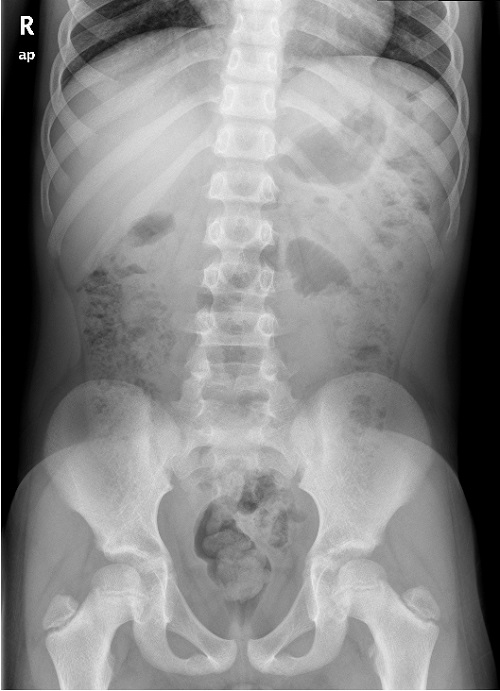

No presentaba síntomas gastrointestinales y su curva ponderoestatural era normal. Fue valorado previamente por Psiquiatría, donde se consideró que el paciente manifestaba un trastorno de la conducta alimentaria en posible relación con ansiedad. Aun así, se remitió a la sección de Gastroenterología Infantil para descartar causas secundarias. Se realizó una radiografía de abdomen simple, que descartó la presencia de un bezoar (Fig. 2), y un análisis de sangre, con hallazgos compatibles con anemia ferropénica (hematíes: 4,68 × 106/μl, hemoglobina: 9,1 g/dl, hematocrito: 29,7%, hemoglobina corpuscular media: 19,4 pg, volumen corpuscular medio: 63,4 fl, concentración de hemoglobina corpuscular media: 30,7 g/dl, banda de distribución de hematíes: 21,1%, ferritina: 5 ng/ml, hierro: 25 μg/dl). Por refractariedad a la ferroterapia oral, se realiza serología de celíaca.